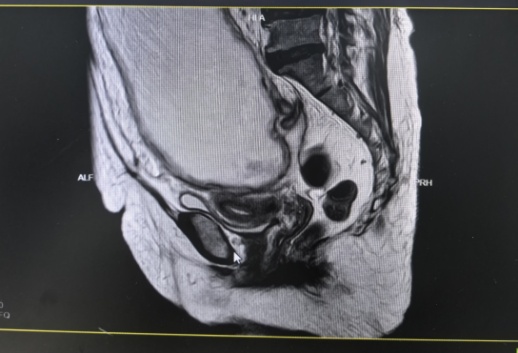

入院检查发现曾阿姨腹部隆起,经过相关检查和多学科联合会诊讨论后,认为曾阿姨腹部巨大包块为肿瘤合并感染可能性大,伴有明显邻近器官压迫症状,手术指征明确。经过与患者及家属充分沟通后,在全麻下行剖腹探查术,术中发现巨大包块来源于左侧卵巢,与肠管粘连致密,包块内可见大量黏液及脓液流出,遂行经腹全子宫切除术+双侧输卵管卵巢切除术+肠粘连松解术+腹腔粘连松解术+阑尾切除术,术后恢复良好出院。术后病理提示左侧附件黏液性肿瘤,阑尾低级别黏液性肿瘤,二者同源。